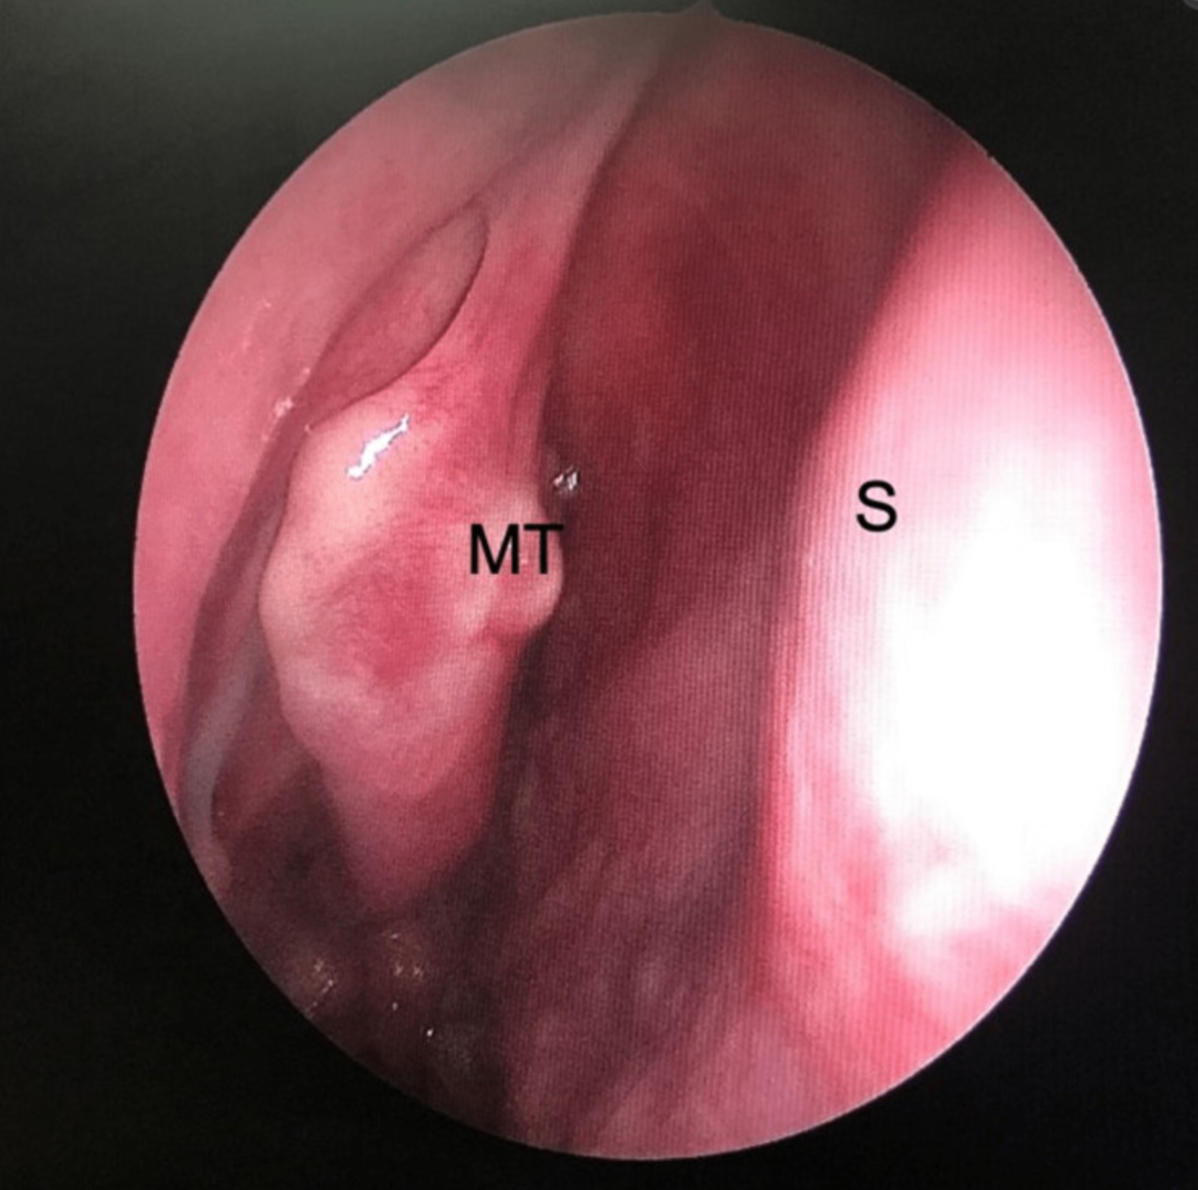

术后病理检查显示,肿瘤边界清晰,间质由淡纺锤形细胞组成,增殖呈局灶性束状。肿瘤细胞之间可见胶原纤维,少见有丝分裂活动。肿瘤细胞在免疫组织化学(IHC)染色中显示出CD34的局灶性阳性,STAT6的强扩散核染色支持SFT的诊断(图3)。

图3